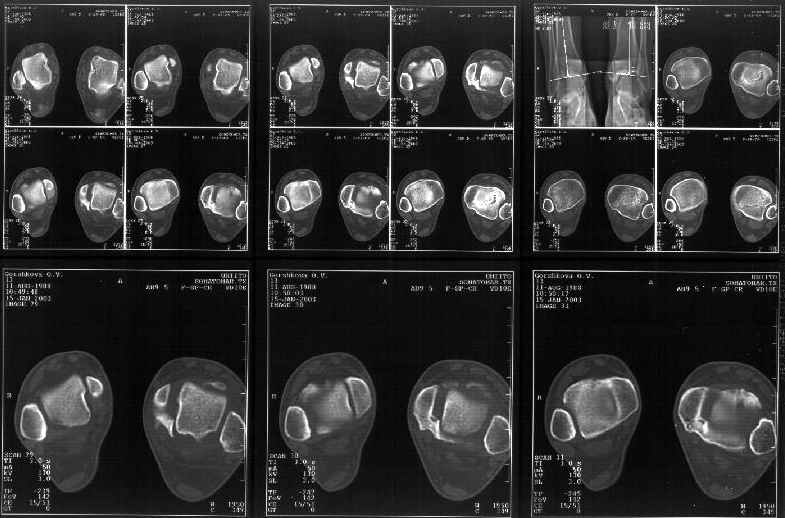

Отправитель: Alexander Chelnokov 19 Январь 2003, 22:34

> К сожалению на последних присланных срезах КТ нет более низкого, через

> таран, среза, который был на прежнем майле. На XR я попытался показать

Сегодня пациентке сделали сравнительную КТ. А ксиальные и Фронтальные срезы приложены. Ваше мнение?

Фронтальные

Аксиальные

Спасибо за КТ -она изумительная. К сожалению, я по дороге на врачебный викенд на Мёртвом море и не смогу подготовить комментарий и схемку до 19.01.03 Помоему, результат КТ даёт чёткую возможность красивой и эффективной помощи.

Отправитель: Й. Воск 19 Январь 2003, 22:50

На КТ я попытался изобразить скромными своими способностями (А)- место перелома, (С)- нормальный суставной зазор меж тараном и тремя его маллеолами. (В)- образовавшийся в результате перелома широкий раза в три зазор, позволяющий, по-моему, сублюксацию тарана при ходьбе. В свете данных КТ, критически важных, я бы предложил вертикальную остеотомию места перелома

задне-внутренним подходом и фиксацию мед. маллеола прижатым к тарану с помощью тонкого compression screw. После этого гипсовый сапожок и немедленное расхаживание ноги.